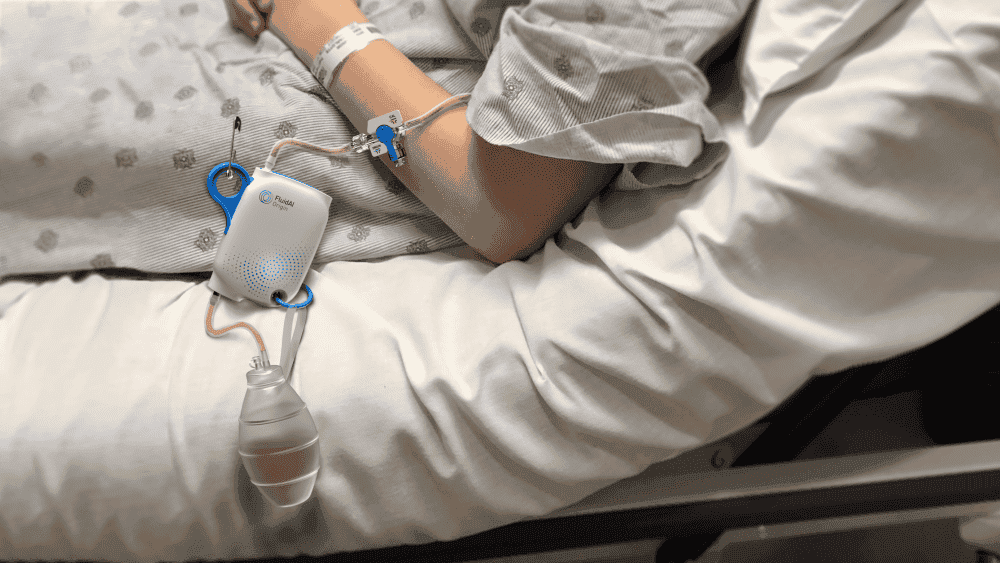

FluidAI- Origin

Design-led development of FluidAI’s non-invasive postoperative infection monitoring platform.